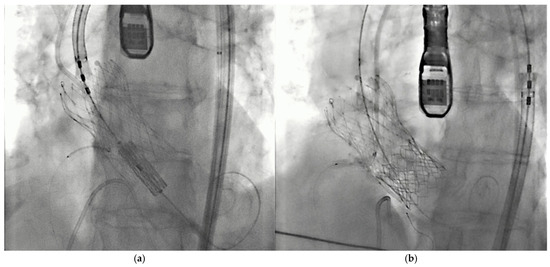

- Burzotta, F.; Kovacevic, M.; Aurigemma, C.; Shoeib, O.; Bruno, P.; Cangemi, S.; Romagnoli, E.; Trani, C. An “Orthotopic” Snorkel-Stenting Technique to Maintain Coronary Patency During Transcatheter Aortic Valve Replacement. Cardiovasc. Revasc. Med. 2021, 28, 94–97. [Google Scholar] [CrossRef]